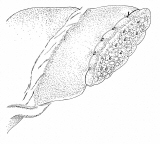

和綴じの方法を応用した、肝部分切除

和綴じの本をお持ちの方は、バラして見るのも一興かも。でも、ご先祖様が化けて出るかも